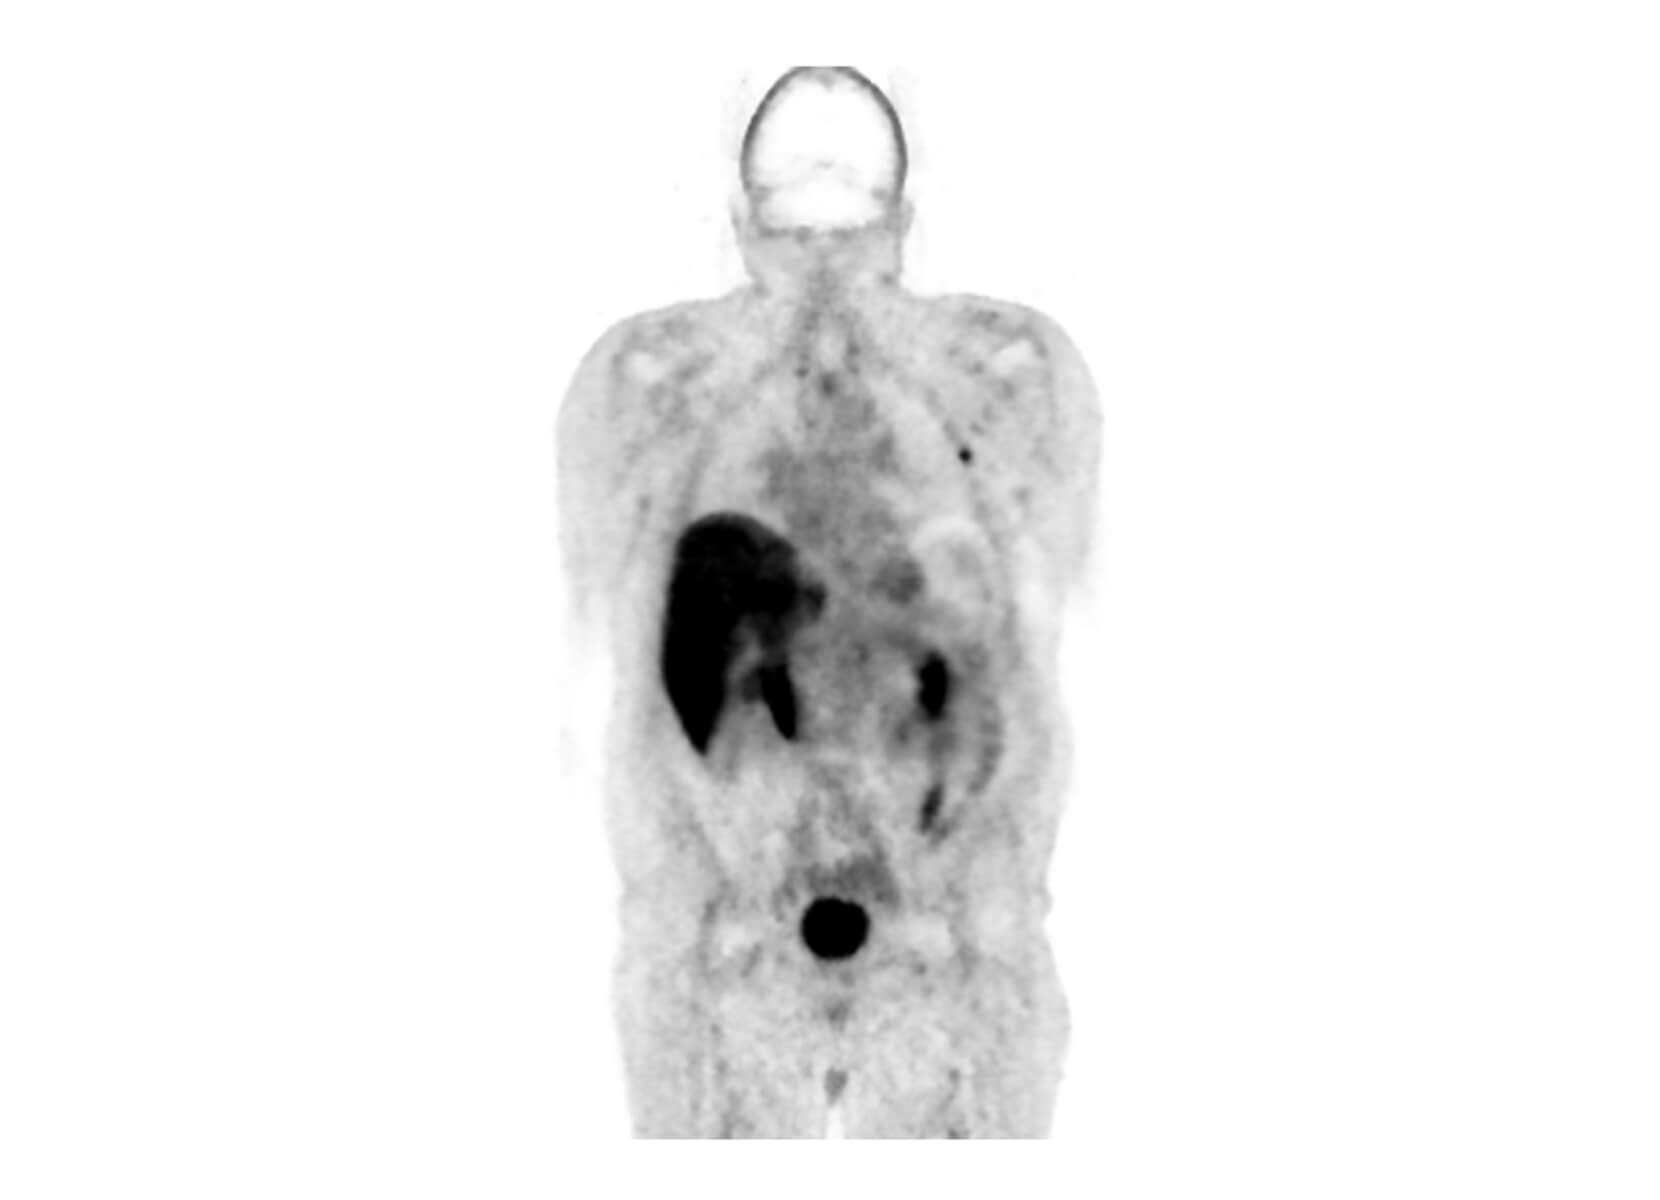

Conventional

ACQ TIME:

20 min

SubtleHD™(PET)

5 min

18F-Florbetapir (AMYLOID)

Philips Vereos PET/CT